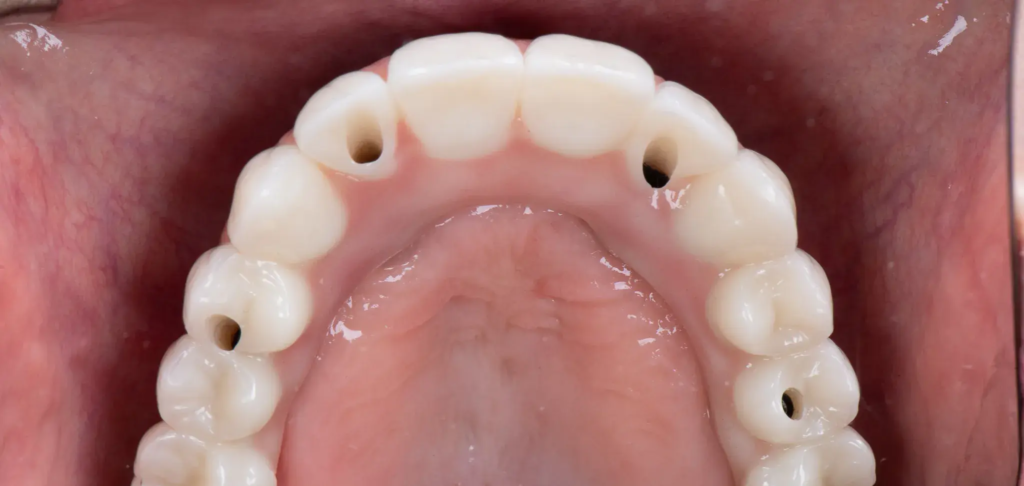

Po zakończeniu osteointegracji nadszedł czas na finalny etap – wymianę mostów tymczasowych na docelowe. Dla Pani Beaty w naszym laboratorium SmileClinic LAB wykonano pełnoceramiczne mosty cyrkonowe. Cyrkon to materiał biozgodny, niezwykle wytrzymały i charakteryzujący się estetyką idealnie naśladującą naturalne zęby. Mosty te są w pełni pozbawione metalu, co gwarantuje doskonały, naturalny wygląd, bez ryzyka przebarwień czy sinych obwódek przy dziąsłach. Ostateczny efekt to trwały, piękny i w pełni funkcjonalny uśmiech na lata.

Widok mostów cyrkonowych licowanych porcelaną zamocowanych w jamie ustnej pacjenta